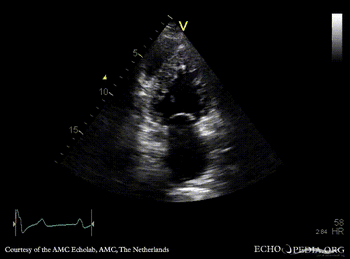

Ebstein anomaly and non-compaction cardiomyopathy

Continuous-wave Doppler signal of tricuspid regurgitation, pulmonary hypertension A2CH: non-compaction of left ventricle